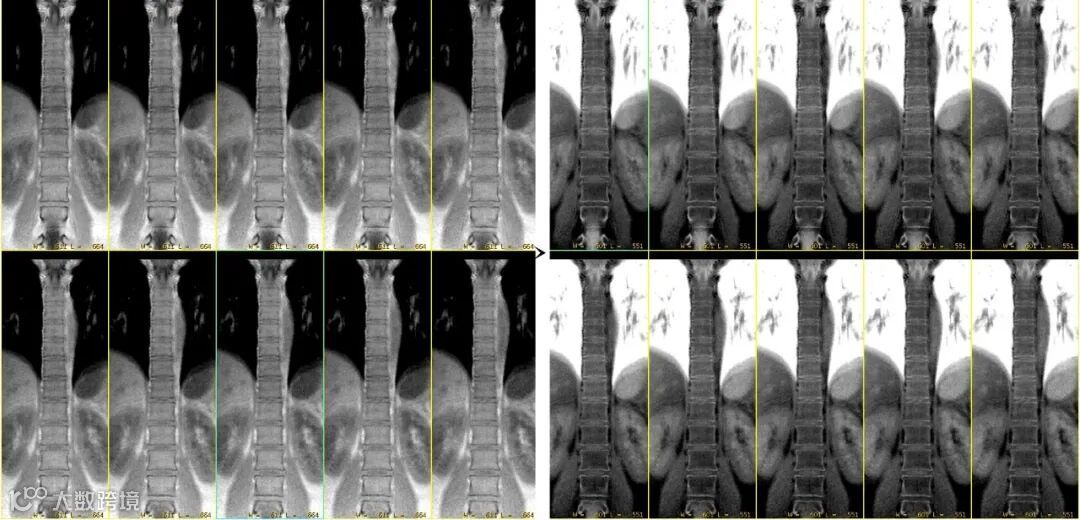

其原始对比度主要反映组织的质子密度和T1弛豫特性。上图△,FA=1°,体素0.8*0.8*0.8mm。

经过从黑到白的灰度反转后,能产生与X线片或CT极为相似的对比度,从而实现直观的“类CT”视觉效果。

上图△,肺部成像。成像FA =2°,体素1.0*1.0*1.0mm。